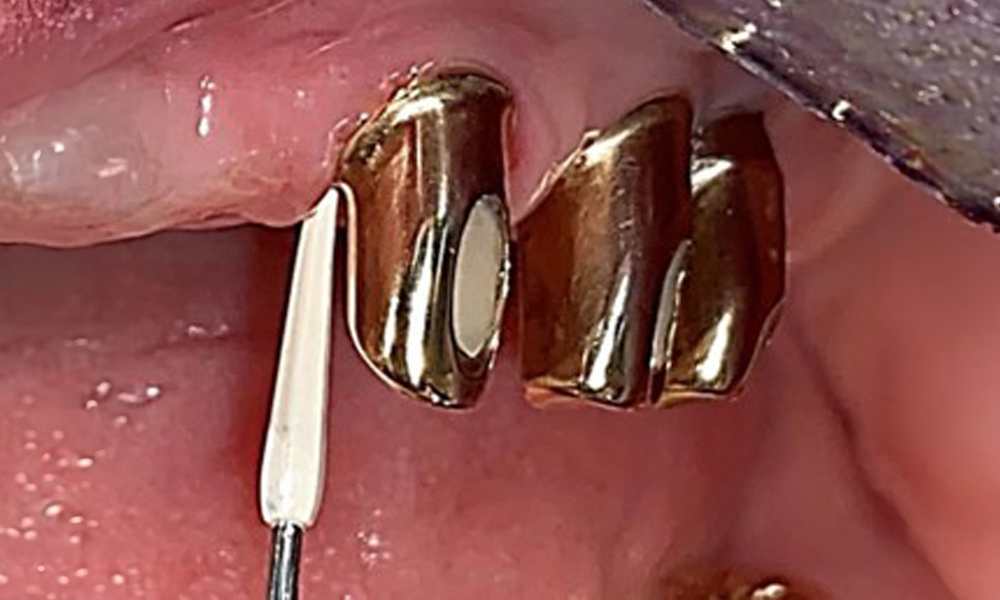

A single-tufted brush is specifically recommended for the telescopic prostheses (Fig. 8) and the patient should be advised on the appropriate interdental brush size (Fig. 9). The patient has been implementing these recommendations for intraoral hygiene at home for many years and was encouraged to continue during the professional preventive dental appointment.

Illustration of a single-tufted brush for home care of the implants and telescopic prostheses.

Fig. 8: Illustration of a single-tufted brush for home care of the implants and telescopic prostheses.